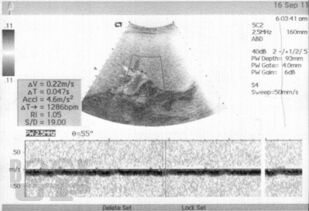

Монография посвящена возможностям малоинвазивного лечения цирроза печени, в т. ч. в стадии декомпенсации с явлениями коагулопатии и тромбоцитопении. Биологические основы эффективности разработанного метода подтверждены в эксперименте и клинике. Доказано, что введение криопреципитата в ткань печени при циррозе вызывает регенерацию функционально сохранных участков паренхимы с образованием упорядоченной балочной структуры и сохранением физиологического соотношения элементов паренхимы и стромы органа. Это способствует улучшению клинико-лабораторных данных и морфологической картины заболевания, в т. ч. улучшению внутрипеченочного кровотока и снижению явлений портальной гипертензии.